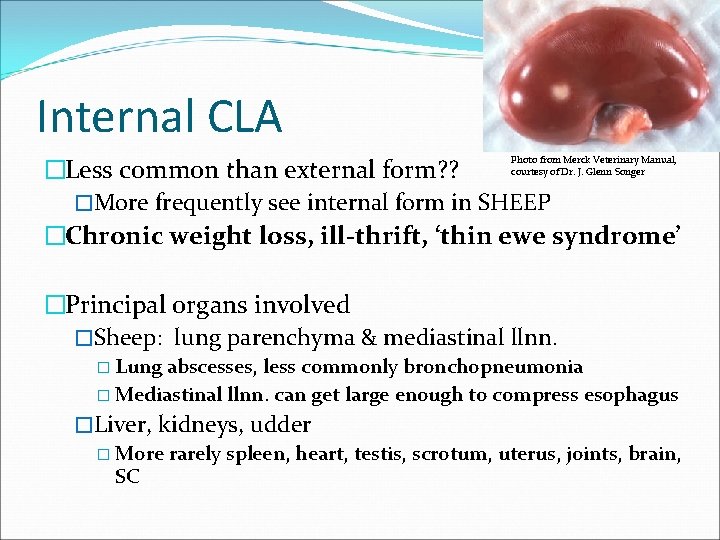

Internal CLA �Less common than external form? ? �More frequently see internal form in SHEEP �Chronic weight loss, ill-thrift, ‘thin ewe syndrome’ Photo from Merck Veterinary Manual, courtesy of Dr. J. Glenn Songer �Principal organs involved �Sheep: lung parenchyma & mediastinal llnn. � Lung abscesses, less commonly bronchopneumonia � Mediastinal llnn. can get large enough to compress esophagus �Liver, kidneys, udder � More rarely spleen, heart, testis, scrotum, uterus, joints, brain, SC